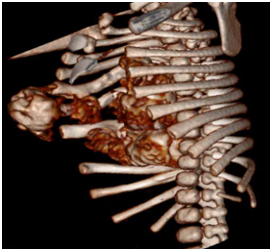

The neonate presented no signs of respiratory distress nor systemic failure. Plain radiograms shows the calcificated mass concerning to the 5th,6th, 7th ribs and the sternum with deterioration of the chest cavity Figures 2a&2b. Ultrasound of the area revealed a heterogeneous lesion, which casted significant acoustic shadow and was located symmetrically to the arches of the 6th, 7thand 8th left ribs. Multislice, low-dose CT scan was subsequently performed to clarify the origin, the extension and the configuration of the mass; 3D reconstructions were particularly helpful as they provided volumetric Figures suitable for preoperative planning Figures 3a&3b.

Figure 3a CT scan reconstruction gives a three-dimensional aspect of the session.

Figure 3b Is seen that the lesion concern at 5th, 6th and 7th right ribs. Scapula and the rest of the ribs aren’t affected.

The main technical challenge in treating young patients with mesenchymal thoracic hamartomas is total excision of the tumor with careful restitution and closure of the thoracic cavity surgical defect6. If this mass is discovered on the antenatal sonographic fetal scan it does not present an indication to perform cesarean section delivery. A preoperative low-dose multislice CT scan with 3D reformats is necessary not only to confirm the benign nature of the lesion and avoid unnecessary needle biopsy but also to perform detailed surgical planning.7 The engendered defect can be covered by the remaining tissues, muscles and peritonea, mobilizing the residual cartilaginous ribs of the lower hemithorax.8,9 A slice of “dura mater” or Gore Dual mesh may be used as a support for the regeneration of the parietal muscles to ensure a more stable thoracic wall10. The use of double lined cement, referred by authors,11 for more rigid parietal reconstruction seems to be excessive and it is not advised. Paradox breathing movement of the affected hemithorax is not a significant postoperative problem for these neonates as it resolves in two to three months time. Furthermore this type of prosthesis shall be removed when the patient grows up. The only adverse to affront is the vertebra scoliosis of the thoracic part of the column. This postoperative late complication can be fronted initially by the use of appropriate bandage or surgical intervention for support the vertebral column.

The mesenchymal hamartoma of the thoracic cavity is a benign lesion that could be detected in the antenatal ultrasound study. The aim of the multislice low-dose CT scan during the neonatal period is critical to provide a 3D depiction of the tumor and to differentiate from other malignant lesions. Total surgical excision of the mass must be the aim of indispensable surgical operation; it should be in a tertiary hospital pediatric unit by multidisciplinary team approach. The prognosis is optimal despite the aggressive surgical intervention during the neonatal period and the follow-up spinal intervention that may be required. Paradox respiratory movement is transitory and the main problem to confront is the scoliosis of the thoracic vertebral column. Close follow up is mandatory.